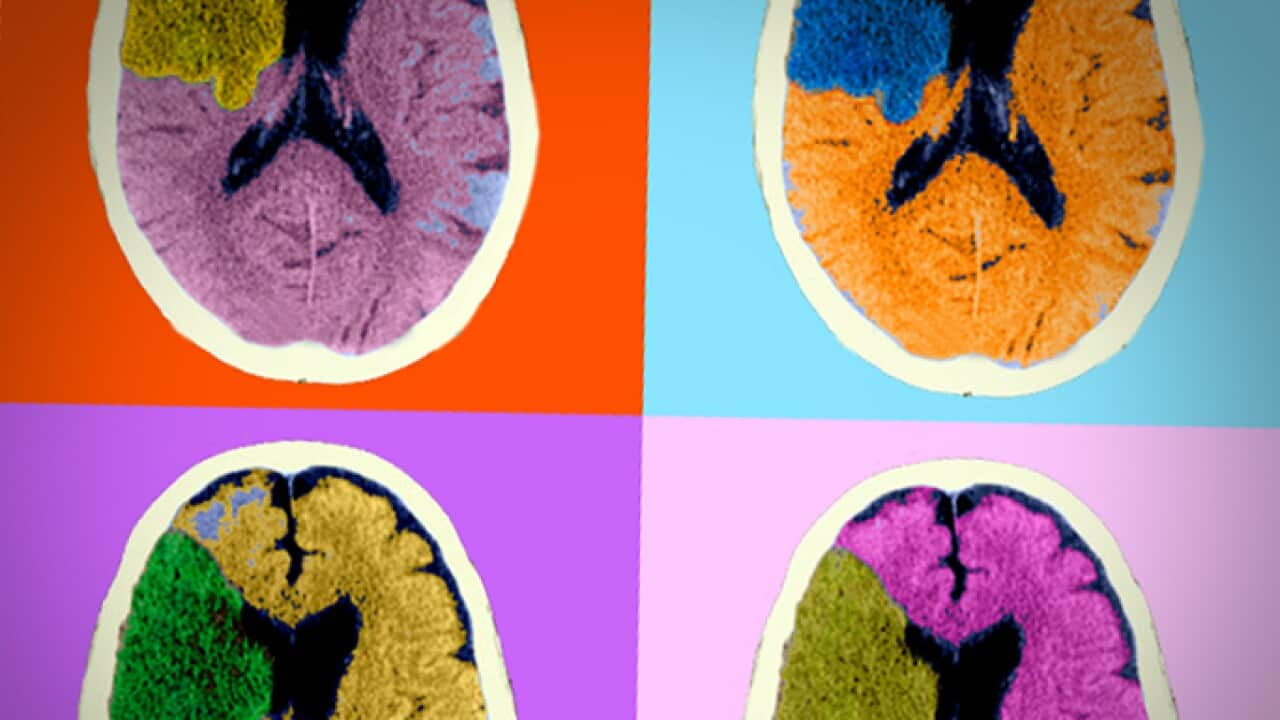

A stroke happens when blood supply to the brain is blocked or interrupted. If the blood supply can be returned in the minutes and hours after the stroke, some brain cells may recover. If not, they will die.

“You'll lose about two million brain cells every minute that goes by,” says neurologist Bruce Campbell.